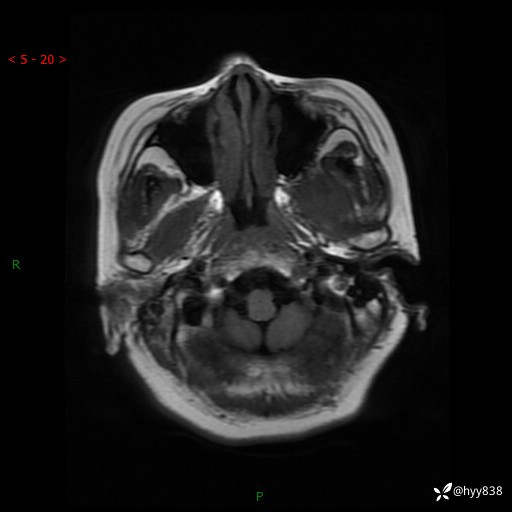

现病史:患者于1个月前无明显诱因出现左眼视力下降,无头痛,无恶心、呕吐,无肢体活动障碍,无意识障碍等伴随症状,后就诊于监利市人民医院行眼眶MRI检查提示“左侧中颅窝底占位性病变”,今日为求进一步诊治前来我院,门诊以“颅内占位性病变”收入院。 发病以来,患者精神、饮食及睡眠良好,大、小便正常。

颅脑MRI平扫+增强